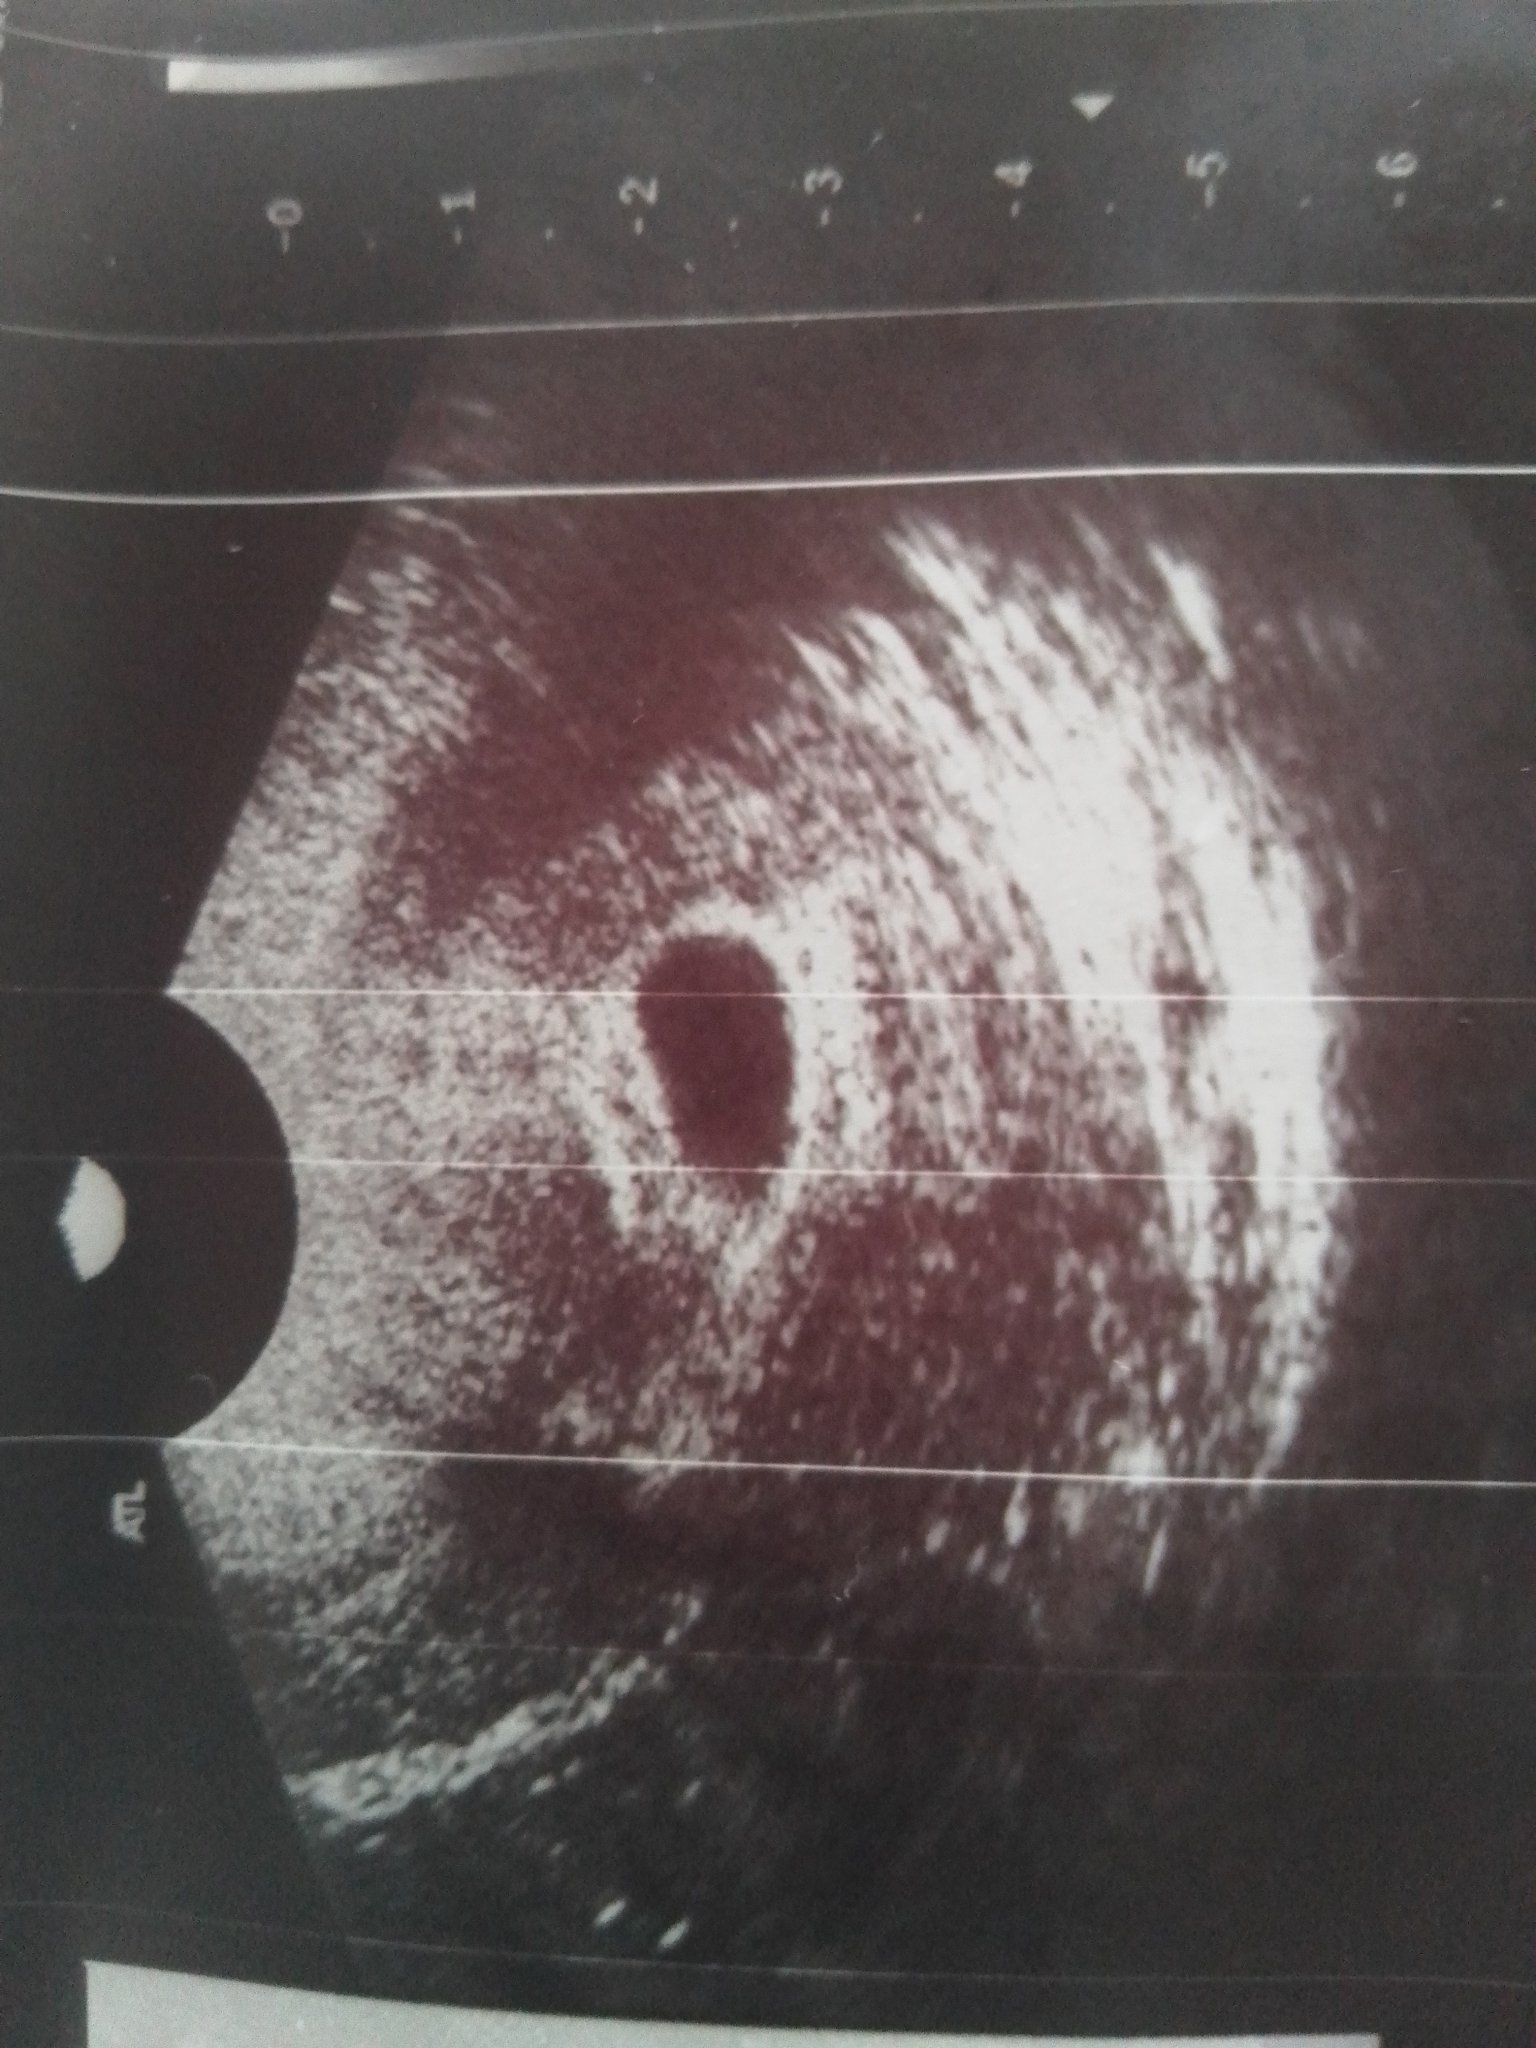

Какви са шансовете да запазите бременността и колко голямо може да бъде отлепването? Защо седмицата не е 7 седмици, както трябва да бъде, а 6 седмици?

Шансовете за поддържане на бременност са индивидуални и зависят от различни фактори, включително размера на отлепването. Отлепването може да варира значително в зависимост от обстоятелствата. Седмицата на бременността се определя въз основа на последната менструация, а не въз основа на датата на прегледа.